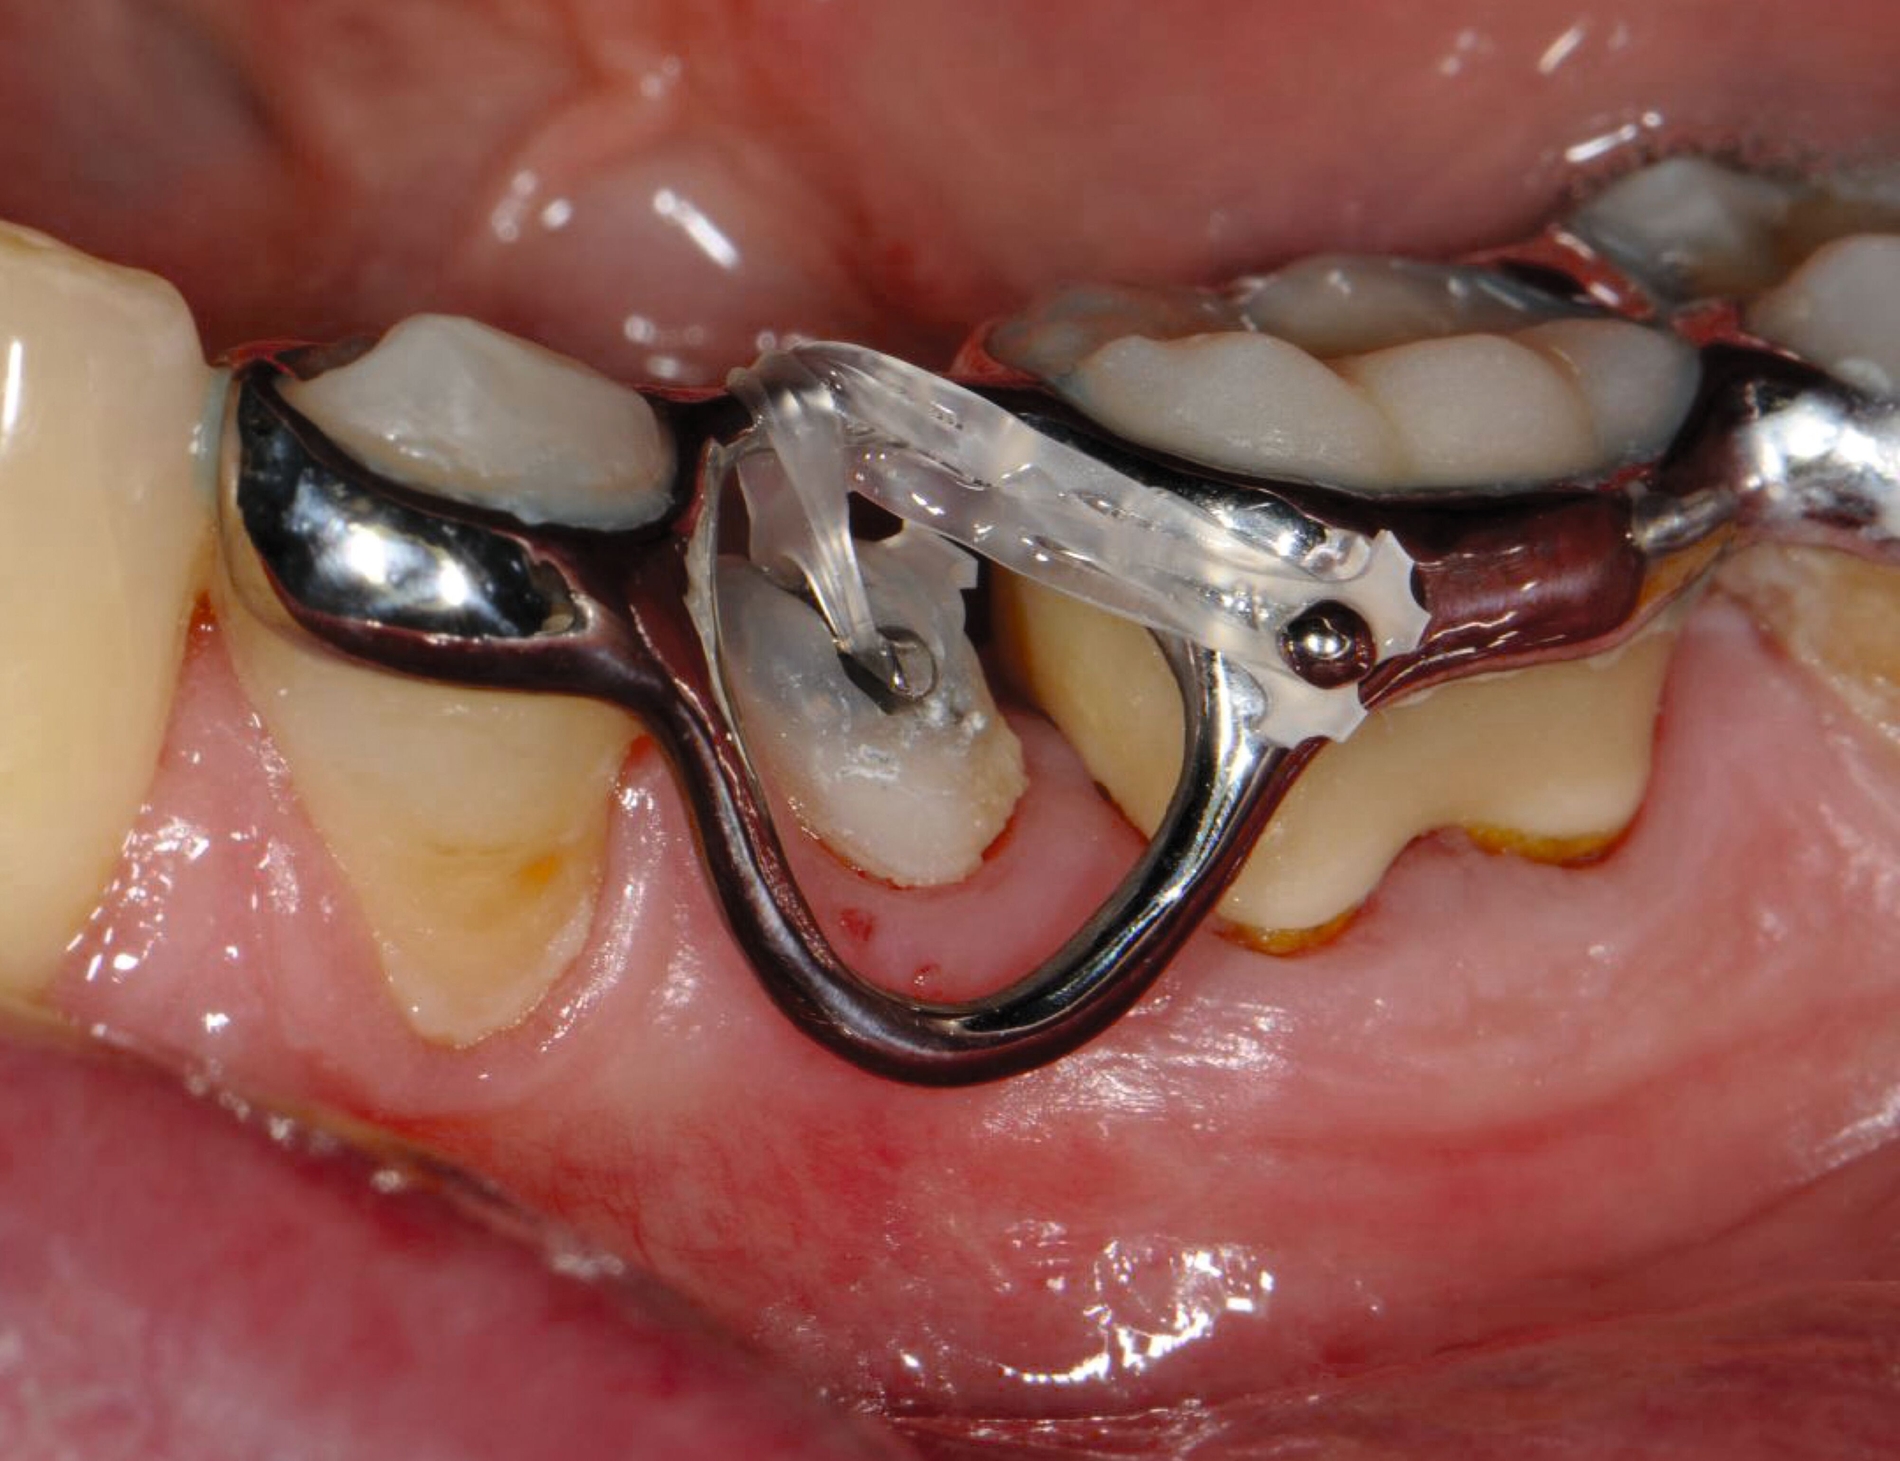

Multibracketapparatur

Als Alternative zu Alignern können auch Brackets mittlerweile im 3-D-Druckverfahren hergestellt werden [Sha et al., 2018; Sha et al., 2019; Bauer et al., 2023] (Abbildungen 2a und 2b). Neben der Nutzung des Angebots kommerzieller Anbieter (beispielsweise Lightforce Company) besteht dabei die Möglichkeit der Herstellung im praxisinternen 3-D-Drucker. Zum Einsatz eignen sich unter anderem Keramik-gefüllte 3-D-Druckkunststoffe der Biokompatibilitätsklasse IIa, die für einen langfristigen intraoralen Einsatz zertifiziert sind (zum Beispiel Permanent Crown Resin, Formlabs) [Papageorgiou et al., 2022; Bauer et al., 2023; Hodecker et al., 2023; Panayi, 2023].

Die Vorteile bestehen vordergründig in einem individualisierten Design, das die jeweiligen Therapieanforderungen berücksichtigt. Bisherige Forschungsarbeiten zeigen eine mit konventionellen Metallbrackets vergleichbare Präzision [Bauer et al., 2023], so dass eine korrekte Übertragung kieferorthopädischer Kräfte gewährleistet ist. Der Haftverbund zeigt sich gegenüber konventionellen Metallbrackets noch etwas schwächer [Hodecker et al., 2023]. Durch weitere Entwicklungen im Bereich der Bracketbasis dürfte diese Limitation jedoch adressiert werden können.

Auch die Herstellung zusätzlicher Elemente, wie beispielsweise Transpalatinalbögen aus Keramik-gefüllten 3-D-Druckkunststoffen, ist möglich (Abbildung 2c) [Thurzo et al., 2022], muss jedoch in großangelegten Studien noch auf eine ausreichende klinische Suffizienz untersucht werden. Weiter bieten 3-D-gedruckte Transferguides die Möglichkeit des „Indirekten Klebens“ [Deahl et al., 2007; Bozelli et al., 2013; Li et al., 2019; Sabbagh et al., 2022], wobei die Bracketpositionierung bereits vor dem Einsatz digital festgelegt und schließlich durch den Transferguide intraoral übertragen wird (Abbildung 2d). Neben einer verkürzten Stuhlzeit erlaubt dieses Verfahren eine besonders hohe Genauigkeit der Bracketpositionierung.